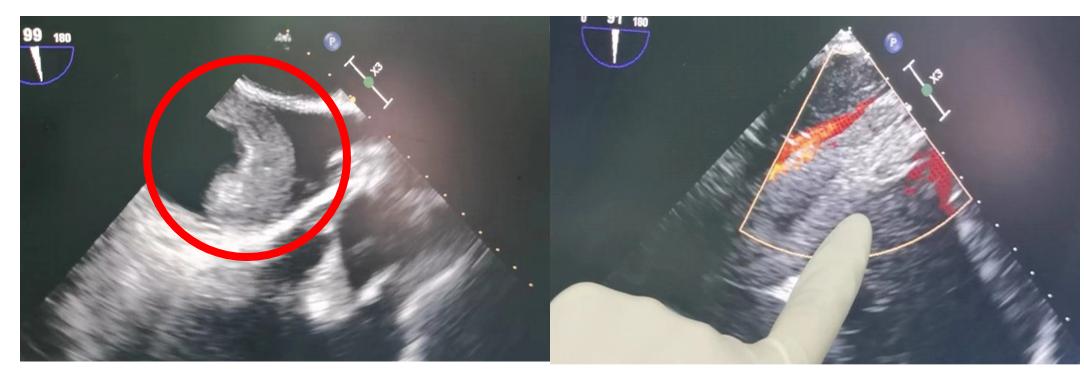

左图:经食道超声显示心脏内长约5cm癌栓盘曲

右图:经食道超声显示下腔静脉内癌栓周围有血流通过,提示癌栓未与下腔静脉壁粘连

启动肾癌癌栓MDT团队,心血管内科冯杰莉主任医师和麻醉科郑清主任医师合作,为赵先生进行了全麻下的经食道超声检查。该项检查可以清晰看到患者下腔静脉与其中癌栓的相对位置。幸运的是,赵先生的癌栓与静脉壁之间未完全粘连,有血流通过,这意味着赵先生的下腔静脉可以得到保留。